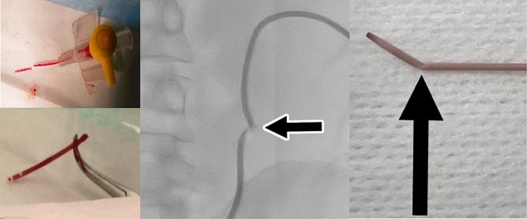

최소 침습 시술을 위한 쉬스와 다일레이터 연계 경피적 진입방법은 Fig. 1에서와 같다. 천자침은 혈관을 천자한 후 가이드 와이어가 진입되기 위한 통로 역할을 하고, 가이드 와이어는 천자침 제거 후 쉬스와 다일레이터의 천자 부위 접근을 도와주며, 다일레이터는 피부에서 피하 조직을 통해 혈관으로 유로를 형성하여 경피적 진입을 유도하고, 쉬스는 진단 및 치료에 사용되는 카테터가 부드럽게 삽입되고 보호하는 역할을 하면서, 고정된 상태로 진단 및 치료가 끝날 때까지 유지한다. 특히 쉬스의 경우, 시술 시 지속적으로 삽입되어 혈관 내부로 삽입되는 다양한 카테터 등의 의료기기가 내벽의 손상 혹은 출혈없이 삽입될 수 있도록 유지해 주는 역할을 수행한다. 이와 같이 쉬스와 다일레이터는 카테터 삽입 시 자극으로 인한 혈관 벽의 상처 및 감염을 최소화하고, 안정적인 술기가 펼쳐질 수 있도록 유로를 확보해주는 최소 침습 기술의 필수적인 의료 기기이다[5].

Fig. 1

Procedure for using the introducer sheath & dilator